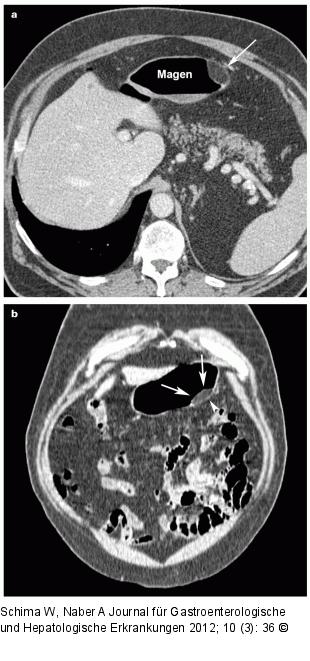

Abbildung 2a-b: Magen - Polypoide Raumforderung (a) Die MDCT zeigt eine polypoide Raumforderung im Magen, die Fett-äquivalente Dichtewerte aufweist (Pfeil). (b) Die 3D-Rekonstruktion in koronaler Ebene zeigt ebenfalls das Lipom (Pfeile) und auch die darunterliegende intakte Magenwand (Pfeilspitze). |

(a) Die MDCT zeigt eine polypoide Raumforderung im Magen, die Fett-äquivalente Dichtewerte aufweist (Pfeil). (b) Die 3D-Rekonstruktion in koronaler Ebene zeigt ebenfalls das Lipom (Pfeile) und auch die darunterliegende intakte Magenwand (Pfeilspitze). |